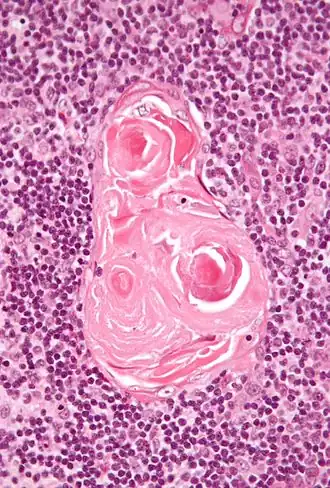

Micrographie des corpuscules de Hassal

Les corpuscules de Hassal, appelés aussi corpuscules thymiques, sont des structures arrondies, éosinophiles, lamellaires et en bulbe d’oignon situées dans la zone médullaire du thymus de l'homme. D'origine endodermique, ces structures épithéliales doivent leur nom au médecin britannique Arthur Hill Hassall (en) qui les a découvertes en 1846[1].